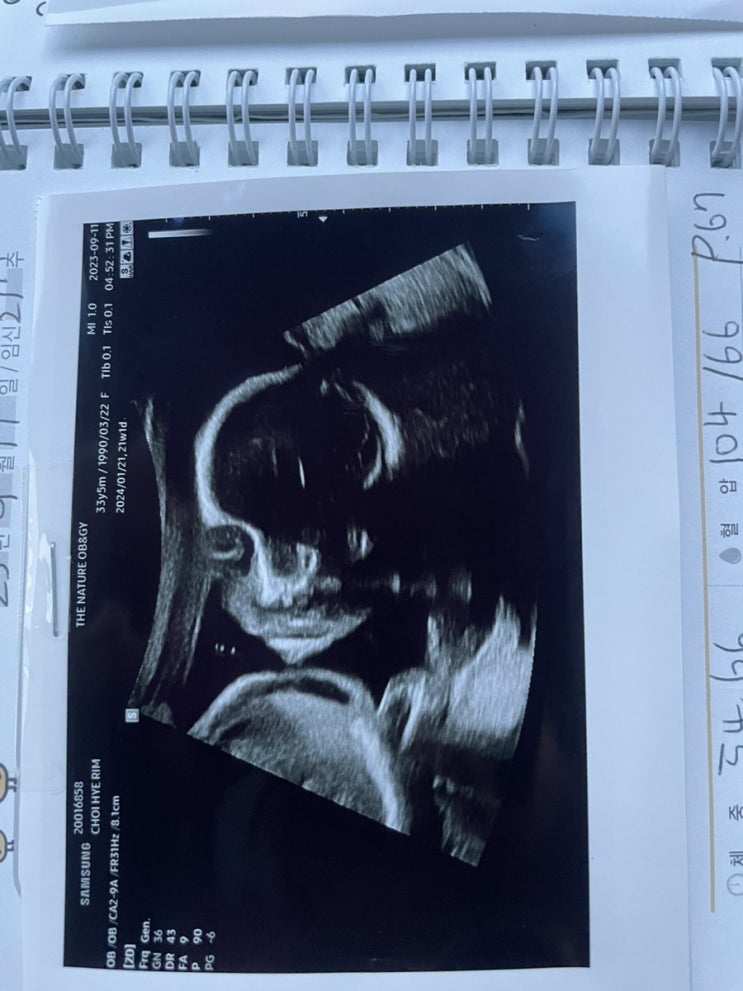

[임신일기] 임신 23-32주차 증상공유(임당통과, 첫 베이비페어, 오케스트라공연관람, 입체초음파, 기저귀가방 쇼핑, 만삭사진촬영)

[임신일기] 임신 19-22주차 증상공유(제주도 태교여행, 태동느낌, 에버랜드, 21주 정밀초음파, 늦은 조리원예약)